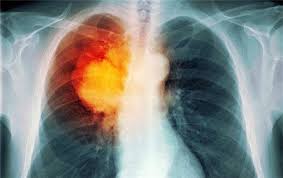

PD-1抑制剂免疫疗法在肺癌治疗中效果怎么样

从目前公布的数据来看,如果不做患者筛选,整体看来,无论是非小细胞肺癌还是小细胞肺癌,使用免疫疗法进行 肺癌治疗 后,大约10%-20%患者肿瘤会显着缩小。      比如,在非小细胞肺癌临床试验中,Nivolumab对鳞癌中客观缓解率是20%,非鳞癌是19%。 ...